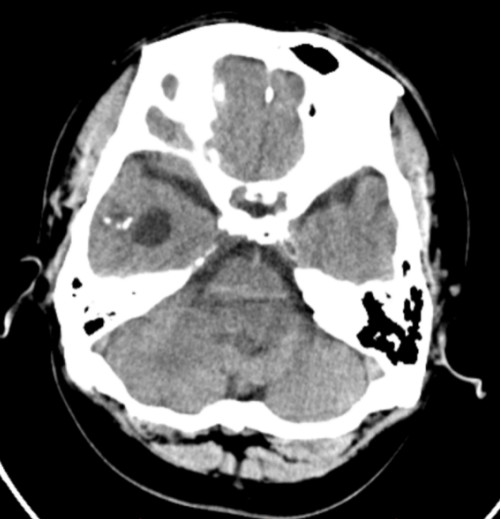

图5. 头颅CT提示右侧颞叶钙化灶。